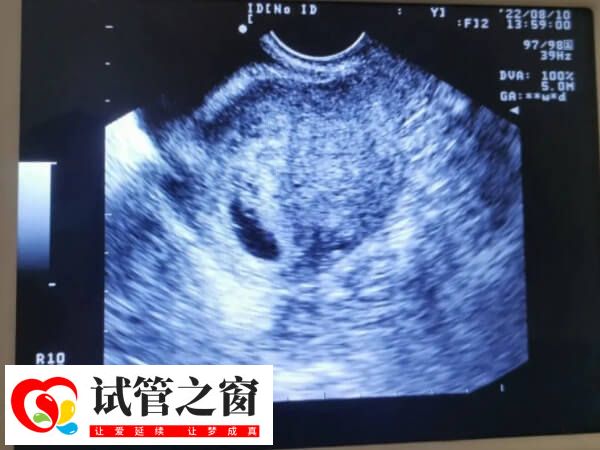

試管嬰兒二超發(fā)現(xiàn)胎芽長度不足1.3cm是正常的嗎?

試管嬰兒二超發(fā)現(xiàn)胎芽長度不足1.3cm時(shí),通常情況是不正常的,但如果是hcg翻倍良好且孕囊大小符合,那么就是正常的。試管二超胎芽通常在1.3-1.7厘米是比較合適的,但由于移植后的胚胎著床時(shí)間以及胚胎發(fā)育快慢等因素存在差異性,所以試管二超胎芽不足1.3cm厘米既有可能是正常的,也有可能是不正常,患者需要及時(shí)配合醫(yī)生查看hcg激素的翻倍情況以及結(jié)合B超檢查的孕囊大小等做進(jìn)一步的判斷。

胎芽是妊娠早期形成的組織,是早孕時(shí)胚胎發(fā)育時(shí)期的一個(gè)必經(jīng)的階段,通常情況下,試管二超的時(shí)候胎芽在1.3-1.7厘米才是比較合適的,此情況下說明胚胎發(fā)育是非常良好的,而不足1.3cm的胎芽就偏小了,但是此情況下,若是女性hcg激素翻倍情況正常,而且B超檢查的孕囊大小等數(shù)值與陪她是符合的,那么試管二超胎芽不足1.3厘米就是正常的。

當(dāng)然若是試管二超胎芽不足1.3厘米,而女性hcg激素翻倍情況不正常,即沒有達(dá)到隔天翻倍,或者是B超檢查到的孕囊大小等數(shù)值與胎芽大小不足1.3厘米不太符合的話,那么就是不正常的,此情況下可能與胚胎質(zhì)量差、激素水平低等因素有一定的關(guān)系,患者需配合醫(yī)生做進(jìn)一步檢查與治療,以使其盡快恢復(fù)正常,必要情況下需終止妊娠。